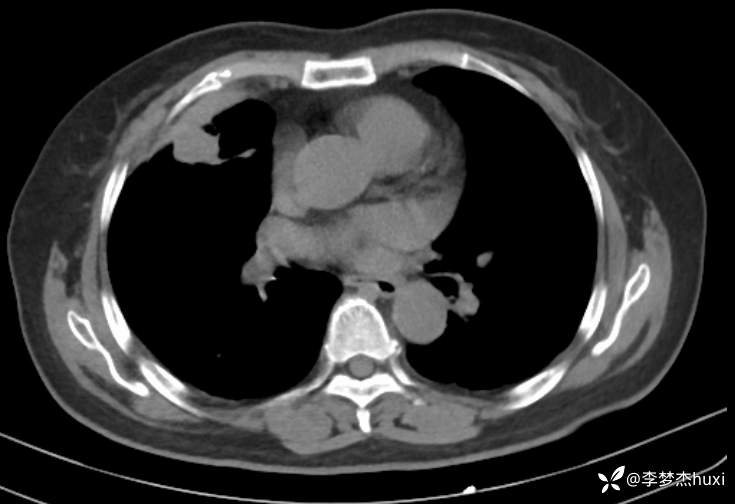

辅助检查:胸部CT:右肺占位?炎症?双肺炎性变,左肺下叶陈旧性病变,双肺纹理增多,主动脉及冠状动脉钙化,双侧胸膜局部增厚,胆囊结石,多发肝囊肿?请结合超声。

临床诊断:肺占位